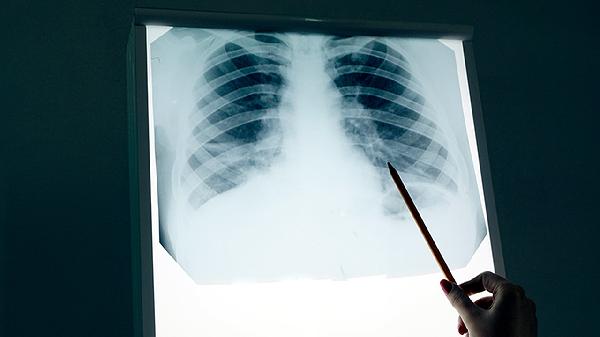

细菌性肺炎可能因肺部炎症渗出物中含有含铁血黄素而使痰液呈铁锈色或深褐色。多伴有发热、胸痛等症状,需进行胸部影像学检查,确诊后可选用阿莫西林克拉维酸钾片、左氧氟沙星片等抗生素治疗。

肿瘤组织坏死或侵蚀血管可能导致痰中带血,陈旧性出血可呈现深褐色。多见于长期吸烟者,可能伴随消瘦、胸痛等症状,需通过胸部CT、支气管镜等检查明确诊断,根据分期选择手术切除、放疗或靶向治疗。